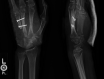

Multifocal chondrosarcoma of the hand: Case report and review of the literature

Few multifocal hand chondrosarcomas have been reported. To our knowledge, this report is the first to describe multifocal hand chondrosarcoma in a patient with no evidence of prior enchondroma, Ollier's disease, or Maffucci syndrome.